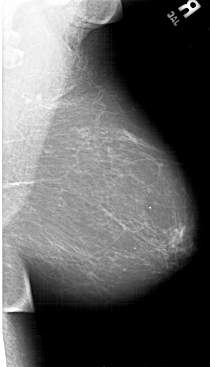

A_1492_1.RIGHT_CC

RIGHT_CC LINES 6466 PIXELS_PER_LINE 3886 BITS_PER_PIXEL 12 RESOLUTION 43.5 NON_OVERLAY